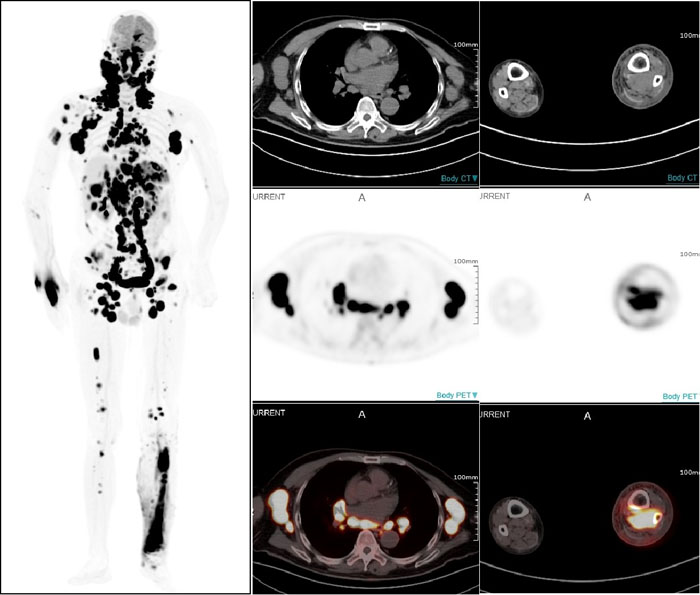

PET/CT显示:全身多部位淋巴结和多个结外器官及不易发现的左小腿后方肌肉组织淋巴瘤受累病灶

一名67岁男性患者因近期无明显诱因出现左颈部淋巴结肿大而就医,淋巴结切检病理诊断为非霍奇金弥漫大B细胞淋巴瘤。借助全景动态Total-body PET/CT扫描,不仅确认了此前的诊断,还发现肿瘤已广泛累及全身多处淋巴结及乳腺、胸膜、肝脏、脾脏、胃等多个结外器官。更令人称奇的是,连平时难以察觉的右小腿深部肌肉组织病变也被准确捕捉。这一全面而精确的影像信息,有效提升了治疗的针对性,为医生制定个性化治疗方案奠定了坚实基础。